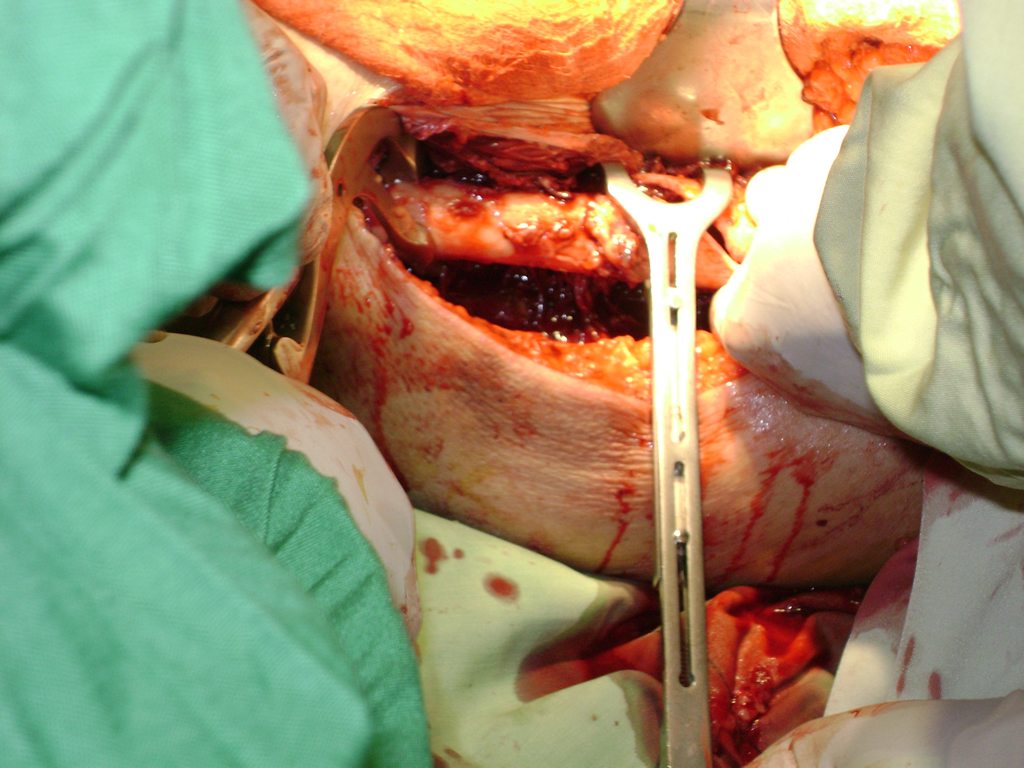

La cirugía de fractura de cadera se realiza para reparar una ruptura en la parte superior del hueso del muslo. Este hueso se denomina fémur.

Es parte de la articulación coxofemoral. Si una fractura de cadera no recibe tratamiento, es posible que deba permanecer en una silla o en la cama.